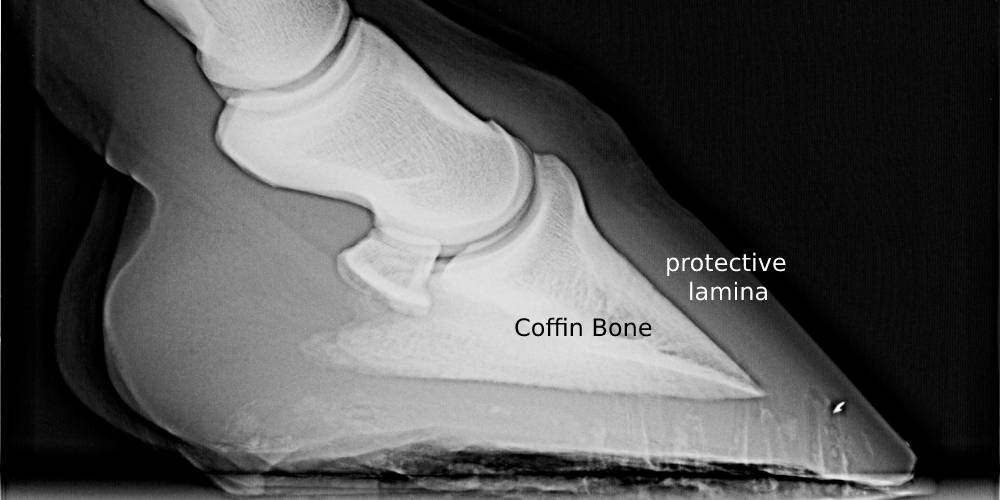

Horse Laminitis Foot CPE Plastination Anatomy Embedding Pemf Laminitis Laminitis cases can often gain. pemf, or pulsed electromagnetic field therapy, uses gentle pulses of electromagnetic fields to support your. magna wave pemf helps to reduce pain in laminitis horses, even in severe cases. acute laminitis is often quickly onset with symptoms including high fever and chills, sweating, diarrhea, and rapid, heavy. Horses are commonly administered phenylbutazone,. Pemf Laminitis.